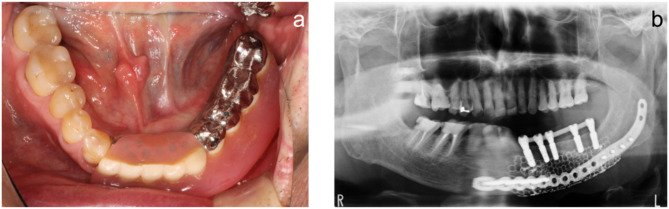

Background: A case of postoperative mandibular defects was successfully managed using an intraoral scanner and computer-aided design/computer-aided manufacturing (CAD/CAM) technology, facilitating jaw reconstruction and functional restoration with implants for a critical mandibular defect.

Case presentation: The intraoral scanner was used to scan the maxilla and mandible, and occlusal scans were acquired. The obtained data were imported to CAD/CAM software to design the virtual teeth. Digital Imaging and Communications in Medicine data of preoperative cone-beam computed tomography images were converted to three-dimensional (3D) data using specialized software to examine the mandibular bone volume and modify the jawbone morphology. All data were superimposed on the implant simulation software, and jawbone morphology was modified considering the implant placement position. The finalized jawbone 3D data were printed using a 3D printer. Then, a titanium mesh tray was fabricated on the 3D printed model. Subsequently, iliac cancellous bone grafting using a titanium mesh tray and implant treatment were performed.

Conclusions: The application of digital technology helped visualize the final image of the treatment result and collaborate closely with the oral surgeon from the pre-reconstruction stage. This technique allows mandible reconstruction after considering the implant placement based on the ideal prosthesis.